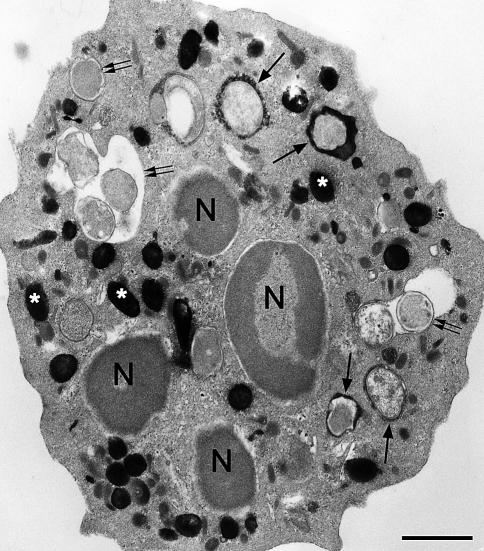

Phagocytic leukocytes consume oxygen and generate reactive oxygen species in response to appropriate stimuli. The phagocyte NADPH oxidase, a multiprotein complex, existing in the dissociated state in resting cells becomes assembled into the functional oxidase complex upon stimulation and then generates superoxide anions. Biochemical aspects of the NADPH oxidase are briefly discussed in this review; however, the major focus relates to the contributions of various modes of microscopy to our understanding of the NADPH oxidase and the cell biology of phagocytic leukocytes.

吞噬性白细胞会消耗氧气,并在受到适当刺激时产生活性氧。吞噬细胞NADPH氧化酶是一种多蛋白复合物,在静息细胞中以解离状态存在,受到刺激后会组装成功能性氧化酶复合物,进而产生超氧阴离子。本综述简要讨论了NADPH氧化酶的生化方面;然而,主要重点是各种显微镜检查模式对我们理解NADPH氧化酶和吞噬性白细胞细胞生物学的贡献。